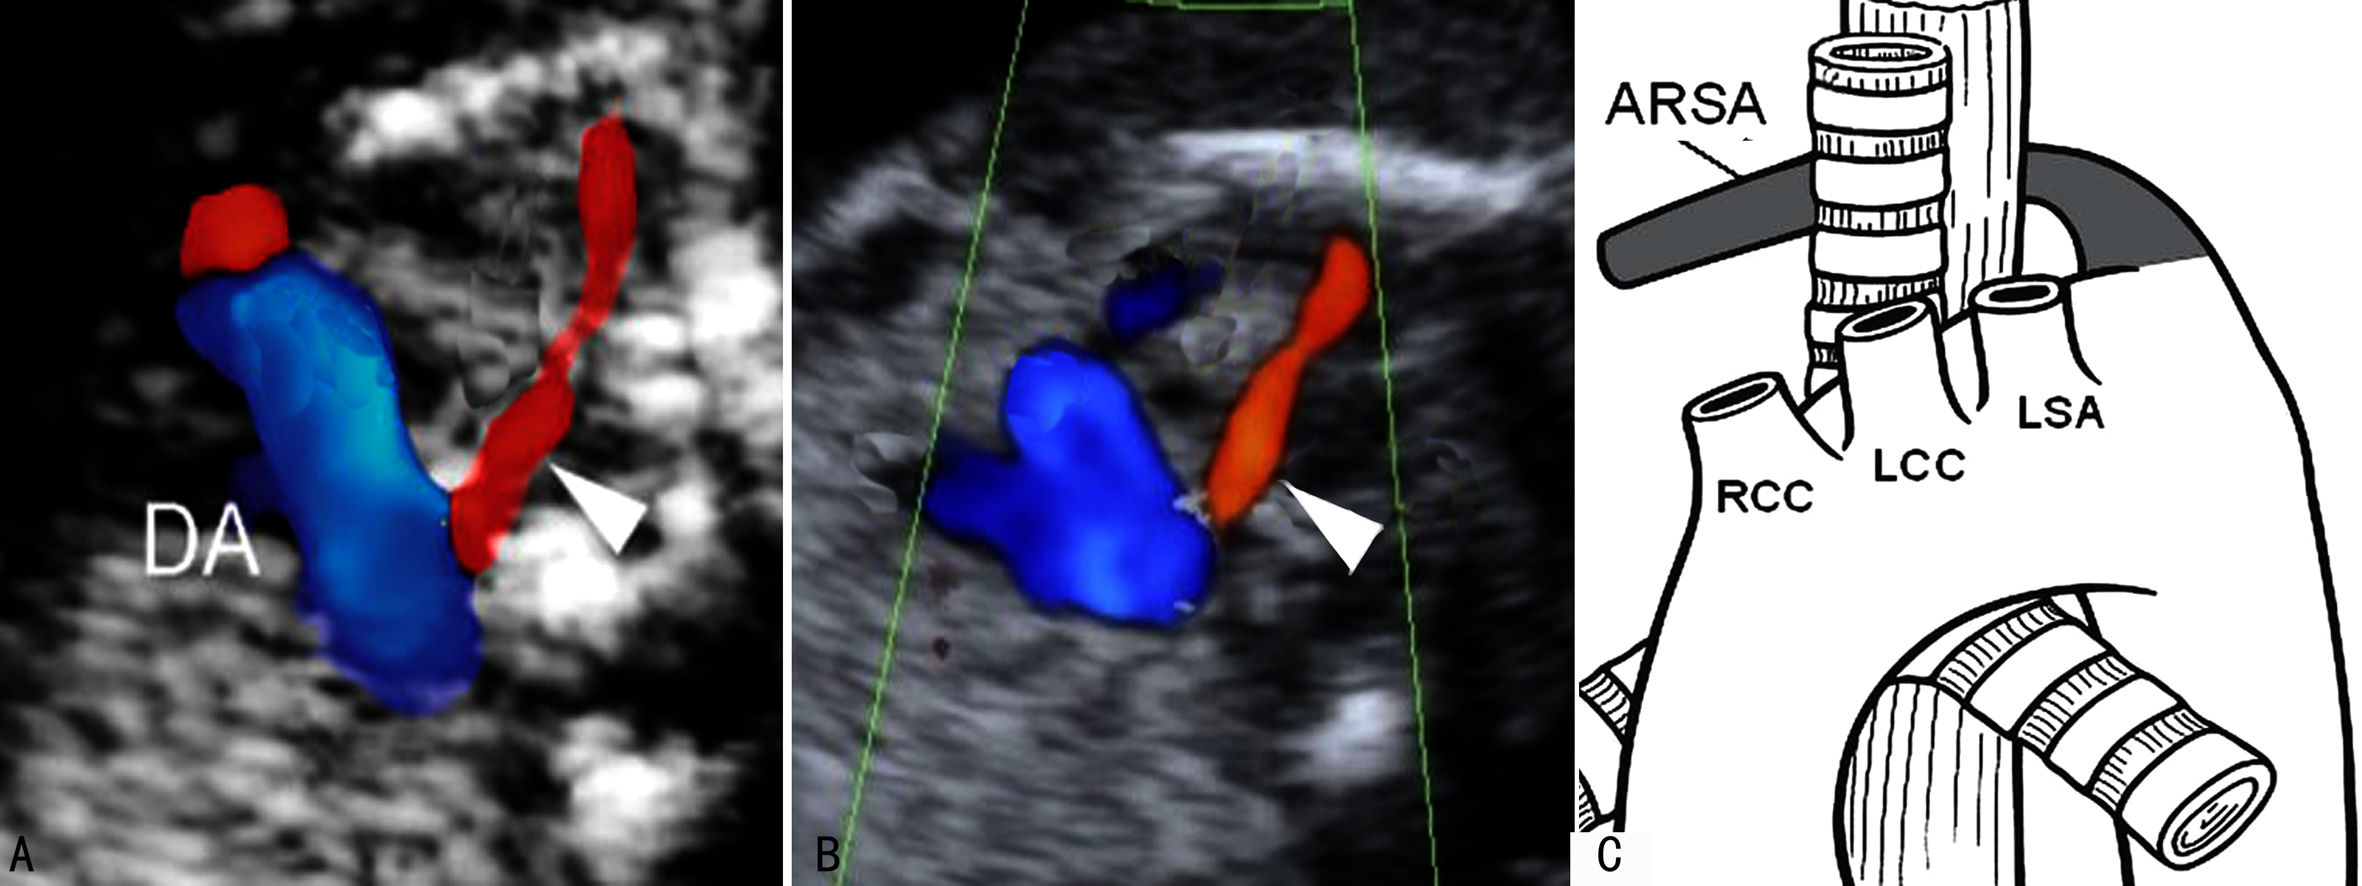

(三)迷走右锁骨下动脉

迷走右锁骨下动脉(aberrant right subclavian artery, ARSA)形成及解剖特点见前述(图5)。

对于中期妊娠中右锁骨下动脉迷走在21-三体综合征的发生情况,Paladini和De León-Luis等做了大量的观察和研究。De León-Luis等在统计了8781例胎儿(平均孕龄24 ± 5.4周)资料后发现,迷走右锁骨下动脉的发生率大约为1%,在7例非整倍体胎儿中,除迷走右锁骨下动脉外均发现合并其他异常;在Paladini等的资料中,21-三体综合征的胎儿迷走右锁骨下动脉的发生率为25%。

图5右侧锁骨下动脉迷走(三角箭头)